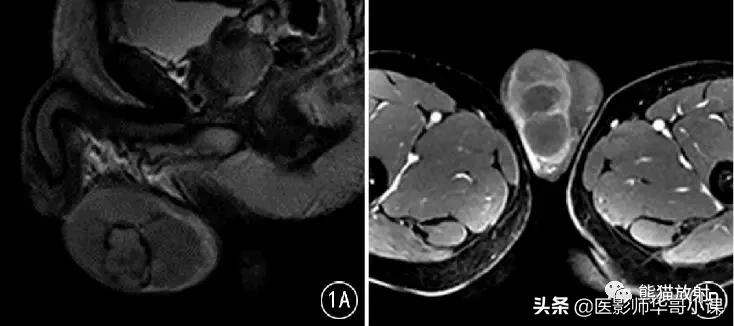

![[精品课件]畸胎瘤及精原细胞瘤(*丸睾**肿瘤及肿瘤样变CT及MR表现)](http://static.shicijianshang.com/origin/pgc-image/afe02658adef4bf883f1d537d12fefee.jpg)

图1 男,32岁, 右侧*丸睾**精原细胞瘤 。T2WI示右侧*丸睾**肿物,其内见低信号纤维分隔及稍高信号出血灶;增强分隔明显强化,且高于肿瘤实质。